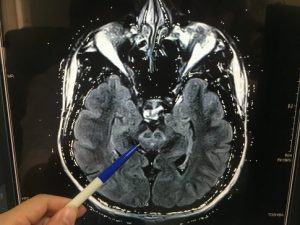

在神經系統方面:過量的銅也會侵害腦部引發神經精神症狀,而出現顫抖、不自主運動、步伐不穩、肢體張力異常、口齒不清、流口水、吞嚥困難等情形;也有患者會出現類似巴金森氏症的行動遲緩或肢體僵硬。更值得一提的是約有三分之一的患者,是以精神病的症狀最早出現,有些威爾森氏症患者會先出現精神症狀,像是情緒不穩、憂鬱症、躁症、精神錯亂等,這些症狀也可從學校功課或工作上的表現受影響看出來。 女性可能會有月經不規則,甚至停經、不孕或流產等現象。